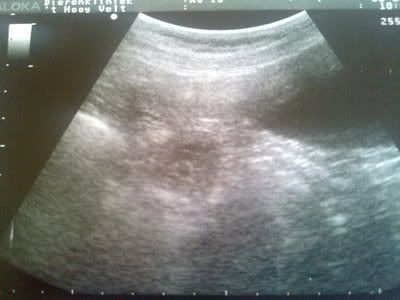

Pamela nu 6 weken zwanger.

En de bevestiging.